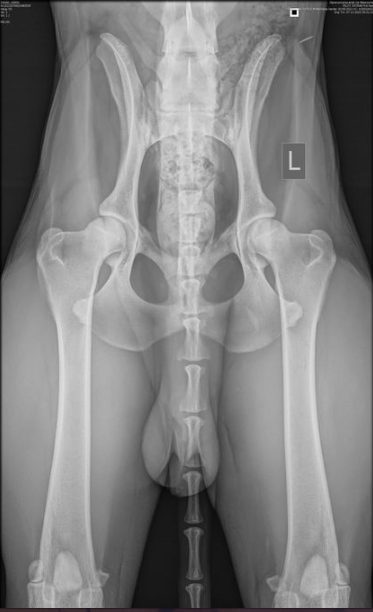

Hips 4/3